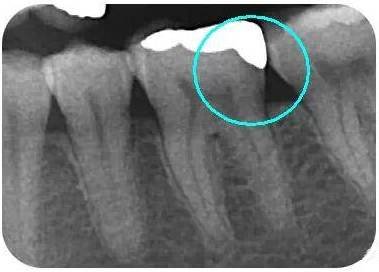

瓷嵌體(ti) 補牙拍片可見,和牙齒邊緣密合度好